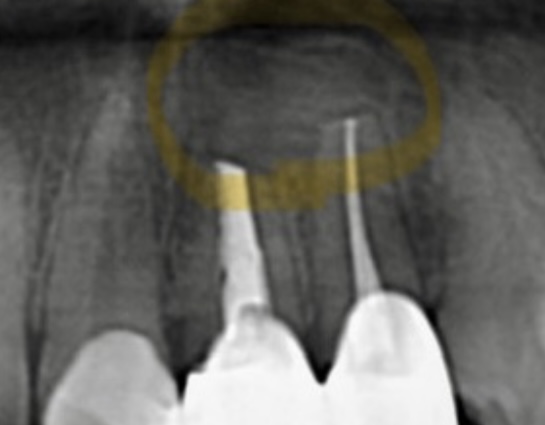

初診時 レントゲン画像

| 主訴 | 左上前歯が痛くて歯茎が腫れている。3年ほど前に神経治療をした。 |

|---|---|

| 所見 | パノラマレントゲンにて左上1番2番に透過像が確認され、根尖相当部歯肉にフィステルあり。また排膿も伴う。打診痛、自発痛あり。 |

| 診断 | 左上1.2部 慢性根尖性歯周炎 |

| 治療内容 | 感染根管処置を行い根管内を無菌化し、貼薬を行った後、マイクロスコープ下にて歯根端切除術を行った。 |

| 治療後経過 | 6ヶ月経過 パノラマレントゲンにて患部の骨の回復が見られた。打診痛、自発痛共に無く経過良好。 |

| 治療期間 | 1ヶ月 |

| 治療費用 | 100,000円 自由診療 |

| リスク・副作用 | 病変が消失しないことがあります。 |